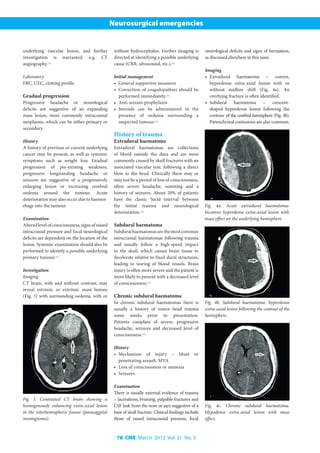

CT brain, with and without contrast, reveals

a ring-enhancing lesion (location often

depends on the underlying cause) with

surrounding oedema in the case of an abscess

(Fig. 2) or enhancing subdural collection

in the presence of subdural empyema.

Fig. 2. Contrasted CT brain revealing ring

enhancing cerebral abscess in the right

parieto-occipital area (arrow).